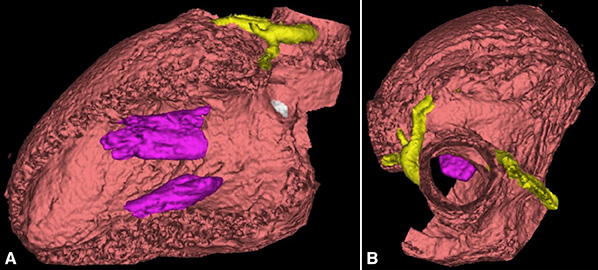

3D reconstruction of the left ventricle with (A) lateral wall removed to visualize septum and (B) surgical transaortic view

Using gated cardiac CT with 3D reconstruction, they were able to reproduce the appearance of the heart under cardioplegia in diastolic arrest; 100 percent of relevant surgical landmarks in all patients were seen preoperatively. Postoperative discussions indicated that preoperative virtual myectomy was helpful in determining how much myocardium to resect as well as clarifying surgical landmarks and anatomy during septal myectomy. Other benefits included detailing the regional difference of septal thickness and width of the “septal band.” The Weill Cornell and Columbia physicians believe this also contributed to achieving a satisfactory clinical outcome.

While septal myectomy is the preferred treatment for patients with obstructive hypertrophic cardiomyopathy refractory to medical therapy — and routinely performed at NewYork-Presbyterian as the least-invasive surgical approach — it is a challenging procedure that relies on a surgeon’s subjective assessment through a limited transaortic surgical view. The mainstay of preoperative imaging assessment remains transthoracic echocardiography, though this modality can significantly mislead in preoperative assessment with regards to location and severity of left ventricle thickness. To address this, Columbia and Weill Cornell cardiologists and cardiac surgeons have developed a virtual myectomy (VM) technique using 3-dimensional reconstruction of gated cardiac CT to assist the intraoperative objective assessment of the adequacy of the resection.